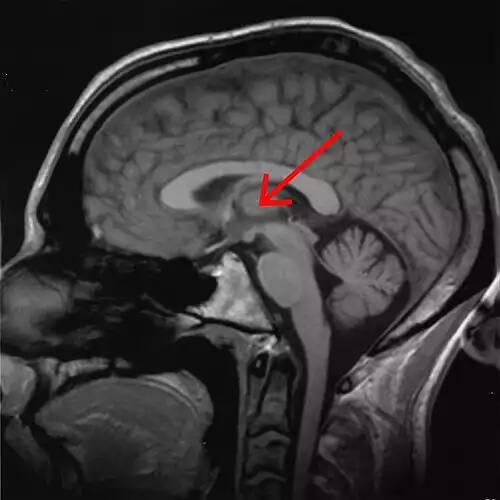

تالاموس ( thalamus ) یا نهنج در مغز و محل تقویت و پردازش اطلاعات است.

اجزای تالاموس:هستهٔ شکمی قدامی ( ventral anterior )، هستهٔ شکمی جانبی ( ventro - lateral nucleus )، هستهٔ شکمی خلفی جانبی ( ventro - postero - lateral )، هستهٔ شکمی خلفی میانی ( ventro - postero - median ) که در داخل هستهٔ شکمی خلفی جانبی قرار دارد و هستهٔ پولوینار ( Pulvinar ) که خلفی ترین هستهٔ تالاموس است.

هر یک از دو تودۀ بیضوی از مادۀ خاکستری، واقع در نیمکره های مخ. این بخش مرکز هماهنگ کنندۀ اطلاعات حسی در مسیر حرکت پیام ها به قشر مخ است و در تنظیم حرکات نیز نقش مهمی دارد.